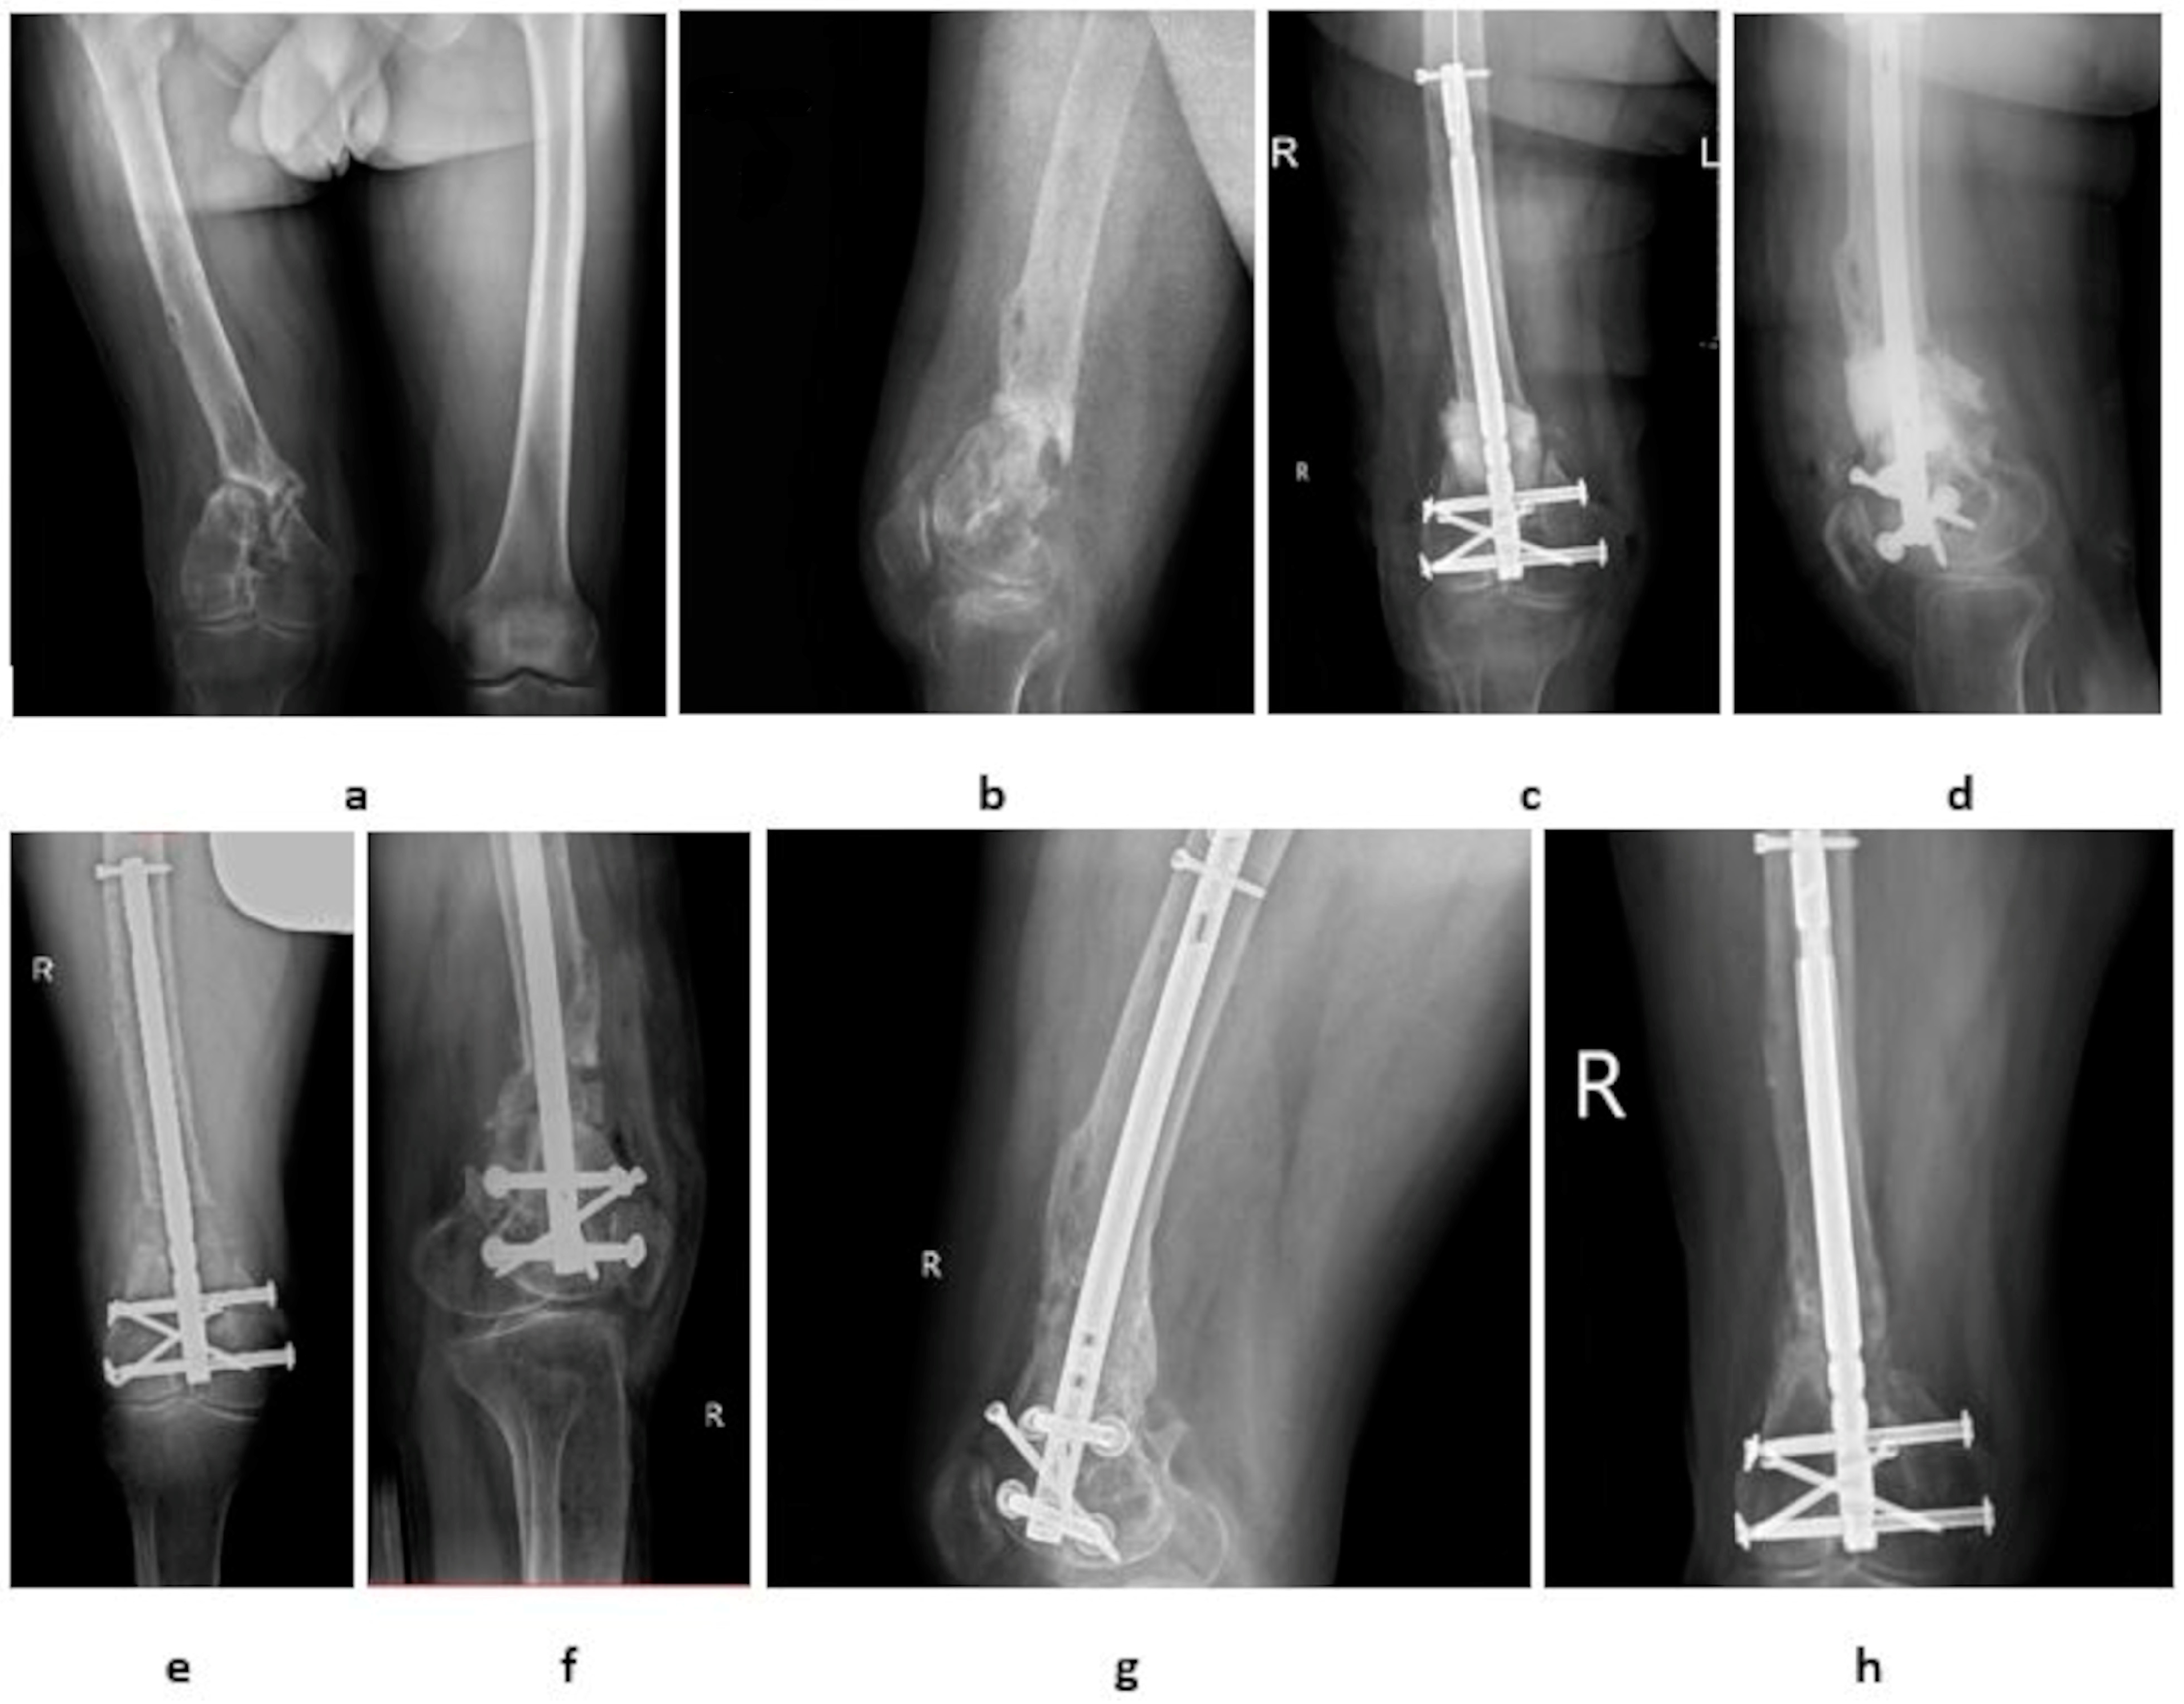

Clinical Observations of the Effectiveness of the Masquelet Induced Membrane Technique in the Treatment of Critical Long-Bone Defects of the Lower and Upper Extremities

| Localization | Arm: 7 | Femur: 11 | ---- |

| Radius: 8 | Tibia: 13 | ---- | |

| Ulna: 5 | Fibula: 1 | ---- | |